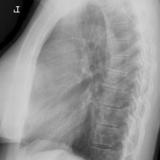

Case 8a Thymoma PA

Date: 03/27/2009

Views: 9450